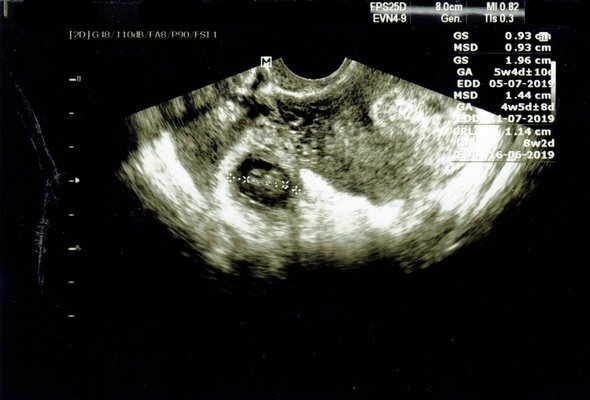

Главный диагностический признак внематочной беременности — это медленный рост ХГЧ (хорионический гонадотропин человека — основной гормон беременности). При маточной беременности он, как правило, удваивается за 48 часов, а при внематочной растет очень медленно. Но окончательно убедиться в том, что у женщины внематочная беременность, можно только после обнаружения плодного яйца в каком-то другом месте, кроме полости матки, — это делается при помощи УЗИ.

Внематочная беременность на УЗИ. Фото: ThoyibAs / Shutterstock / Fotodom